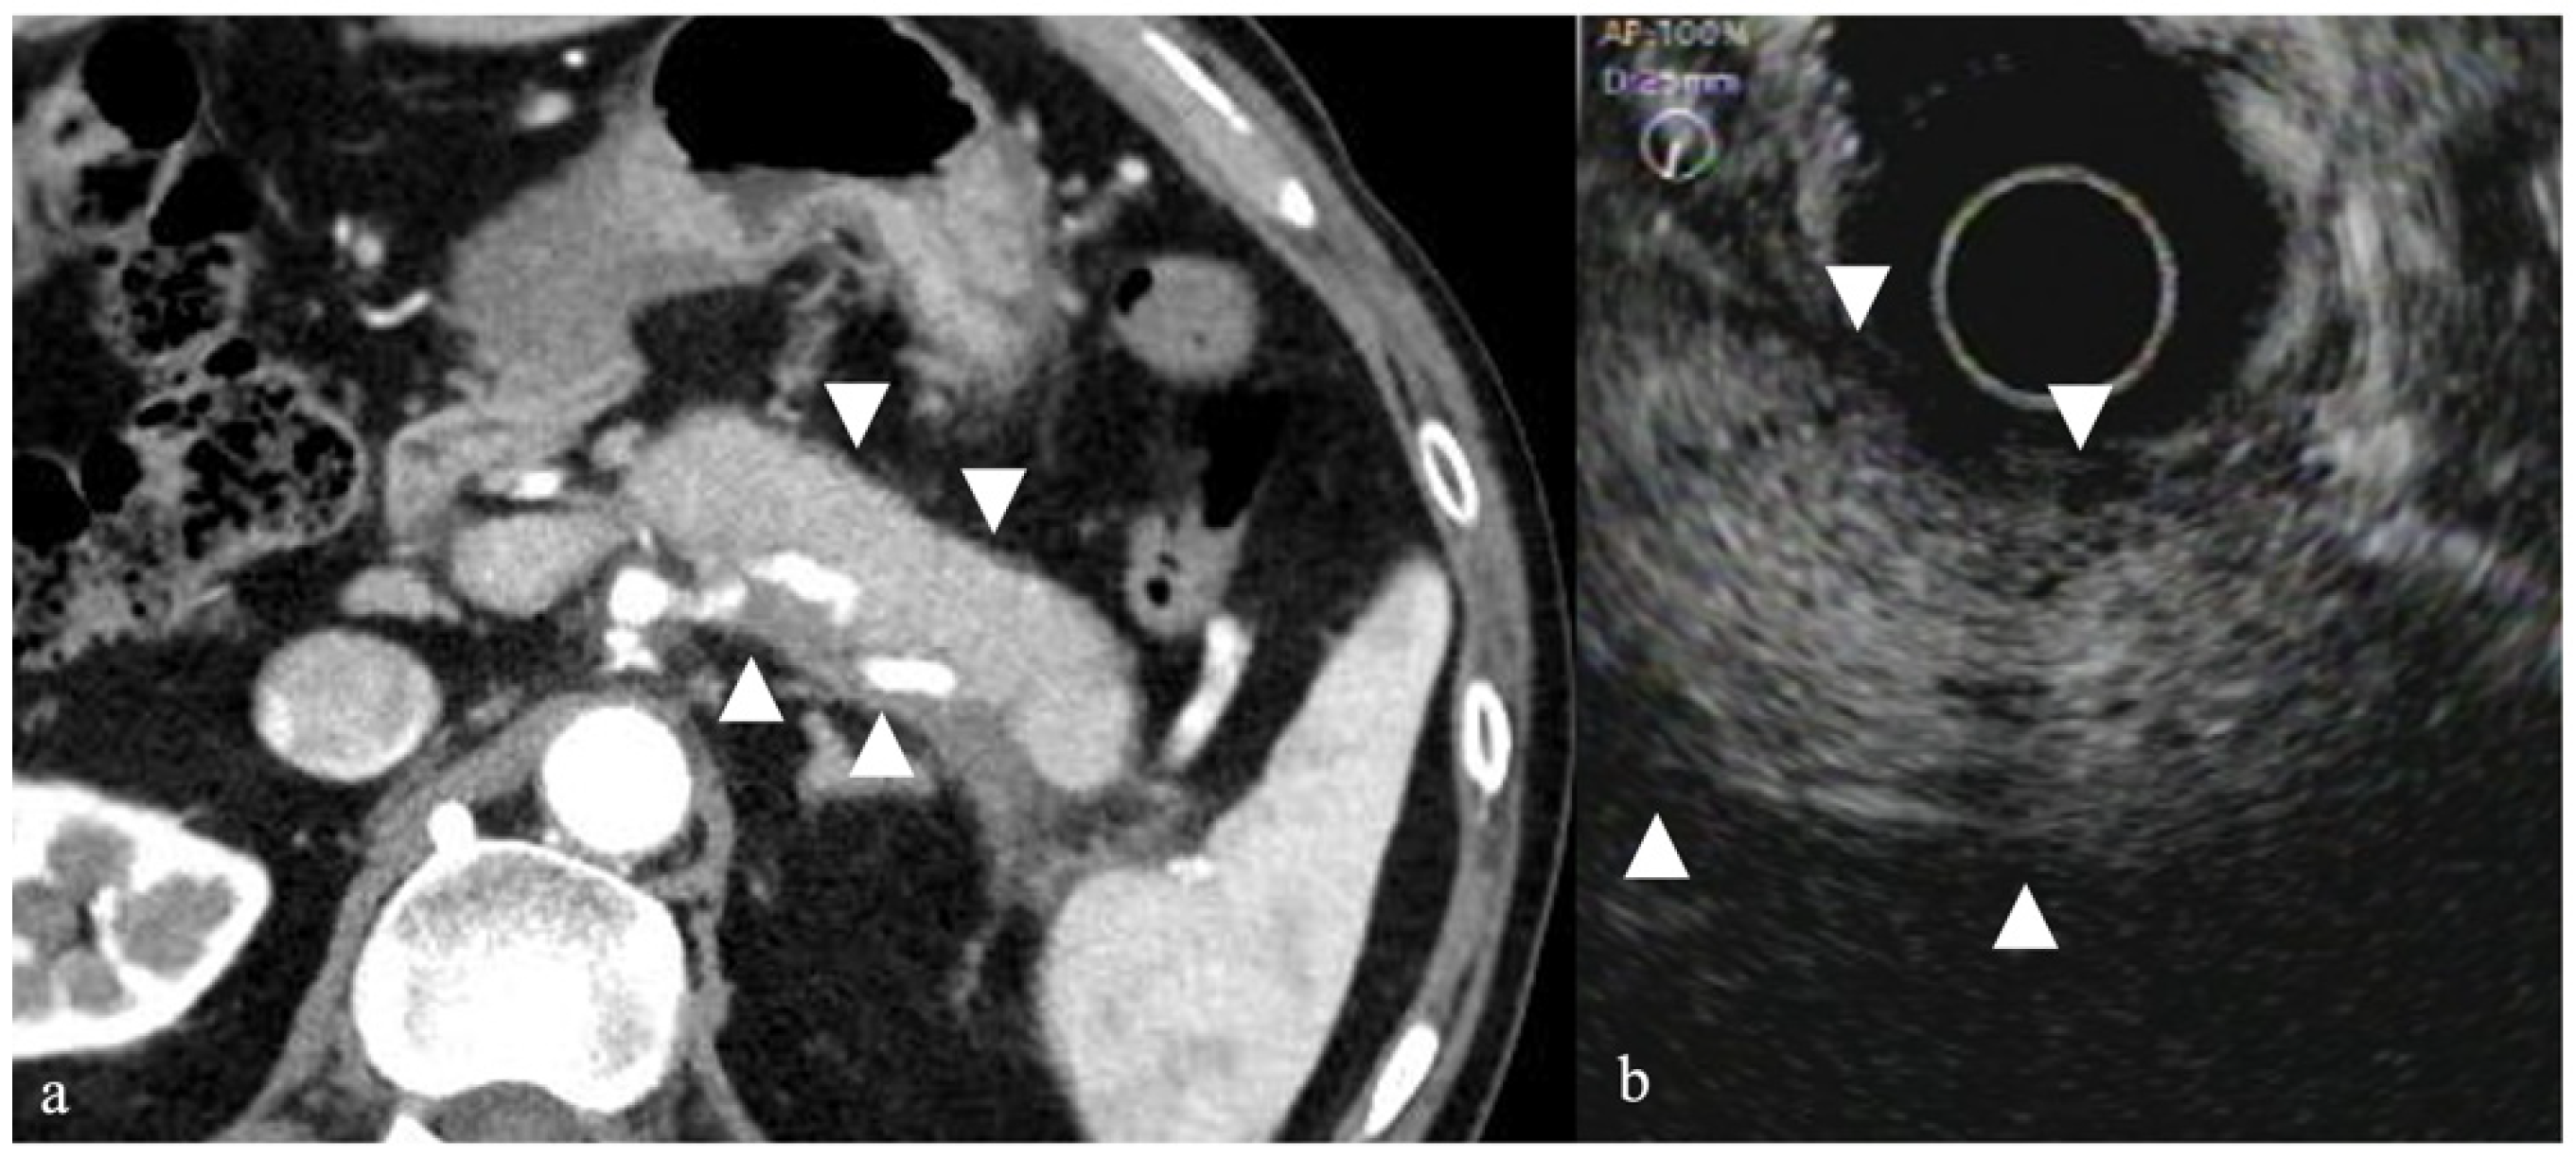

- Imazu, H.; Uchiyama, Y.; Matsunaga, K.; Ikeda, K.-I.; Kakutani, H.; Sasaki, Y.; Sumiyama, K.; Ang, T.L.; Omar, S.; Tajiri, H. Contrast-enhanced harmonic EUS with novel ultrasonographic contrast (Sonazoid) in the preoperative T-staging for pancreaticobiliary malignancies. Scand. J. Gastroenterol. 2010, 45, 732–738. [Google Scholar] [CrossRef]

- Miyata, T.; Kitano, M.; Omoto, S.; Kadosaka, K.; Kamata, K.; Imai, H.; Sakamoto, H.; Nisida, N.; Harwani, Y.; Murakami, T.; et al. Contrast-enhanced harmonic endoscopic ultrasonography for assessment of lymph node metastases in pancreatobiliary carcinoma. World J. Gastroenterol. 2016, 22, 3381–3391. [Google Scholar] [CrossRef]